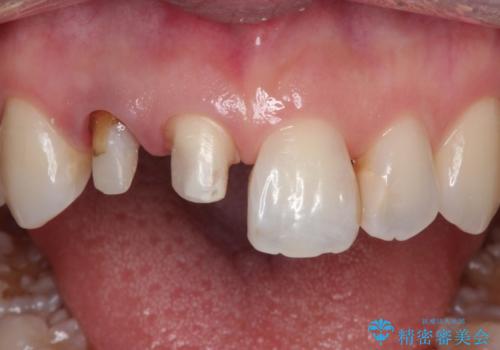

前歯が痛い。根管治療~オールセラミッククラウン

- 前歯が痛いことを主訴に来院されました。

根管治療を行った後、オールセラミッククラウン(エクセレント)にて治療を行いました。